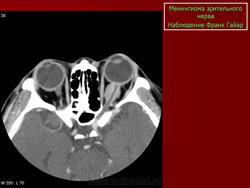

КТ-семиотика

На КТ срезах без контрастного усиления менингиома зрительного нерва выглядит изоденсной. Типично наличие линейных или точечных обызвествлений. Симптом «трамвайных рельс» отражает накопление КВ по сторонам гиподенсного зрительного нерва или наличие обызвествлений в структуре опухоли. Как правило, наиболее дистальная часть зрительного нерва, в месте его вхождения в глазное яблоко, не содержит обызвествлений.

При исследовании необходимо определить расположение бляшковидной менингиомы относительно бугорка турецкого седла и пластинки клиновидной кости, так как данный тип опухоли может распространяться интракраниально через канал зрительного нерва. КТ не позволяет адекватно визуализировать интракраниальное распространение опухоли, которое может привести к развитию двусторонней слепоты.